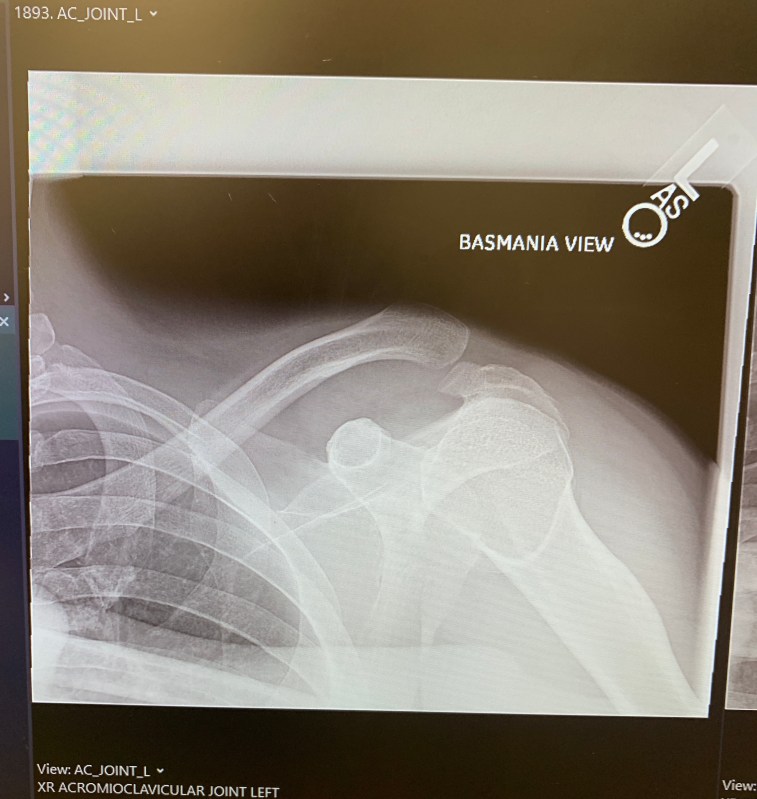

And, of course, he wanted to provide an update for interested readers: The update: don’t panic (yet). As you can see vy the X-ray image above, Kuntzman’s clavicle (jambiuolum Tiberius in Latin, or so he claims) has separated from the arm bone, though to the layman’s eye (his), it appears to have come in completely shorn off. Apparently, Kuntzman will need special surgery, conveniently enough, at the Hospital for Special Surgery, that and he is not making this up, will require a doctor to take the Achilles tendon of a cadaver, screw it into the clavicle, and sew the overhanging tendon (or ligament, we always mix those up) to the torn tendon (or cartilage, we always mix that up, too) and tie that clavicle back into place.